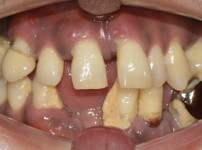

전악 임플란트

황OO님/치료기간:13개...